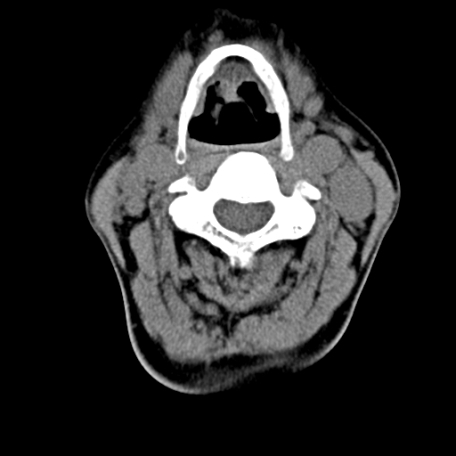

标题: CT24010:患者女56岁双侧甲状腺摘除术后一月复查,患者现感 [打印本页]

标题: CT24010:患者女56岁双侧甲状腺摘除术后一月复查,患者现感

甲状腺区域密度不均匀密度影,应该是术后改变,要鉴别是否复发,建议增强检查。

“甲状腺摘除术后一月复查”,有病理吗?考虑术后复发,可能是恶性,颌下及左侧颈部淋巴结有肿大。

双侧甲状腺肿大,伴多发低密度灶(性质待定);建议行进一步检查。

双侧甲状腺肿大,周围结构不清,术后复发时间有点短,考虑出血并感染。